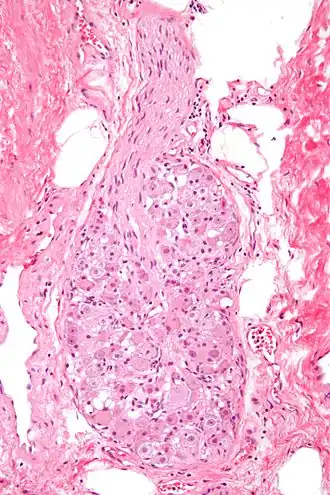

![]() Micrograph of a ganglion. H&E stain.  | |